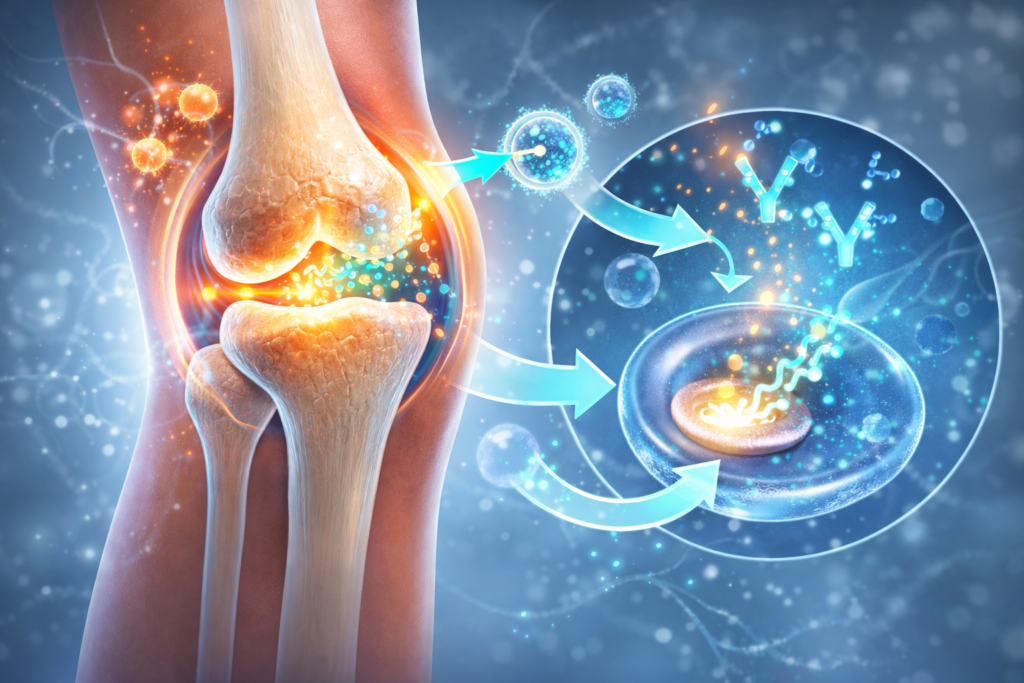

How Gene Therapy Works in the Knee

Gene therapy is a medical technique that helps the body make helpful things on its own. Gene therapy tells cells how to make medicine inside the body instead of having to take it every day.

Doctors give a gene therapy shot directly into the knee joint as part of this new treatment. The treatment has a small amount of genetic information in it. This genetic material tells the cells in the joint to start making proteins that help.

These proteins can help protect the cartilage in the knee and lower inflammation. Cartilage is the soft tissue that protects the bones. When cartilage breaks down, arthritis gets worse.

Scientists hope that the treatment can slow down the damage happening in the knee by helping it make these protective proteins. People with knee arthritis may have less pain and be able to move better because of this.

One more good thing is that the treatment might last for a long time after just one shot. The cells learn how to keep making the helpful proteins, so the effect could last longer than many current treatments.

Initial laboratory and limited clinical studies have demonstrated encouraging outcomes. Researchers found that the joints that were treated made more protective proteins that help reduce inflammation and keep joints healthy.